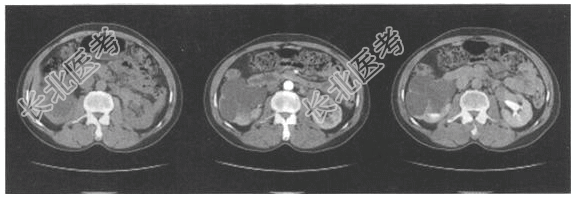

- [材料题] 患者,女,35岁。6年来反复低热、腰痛、伴尿频、尿痛,多次尿常规:尿比重均为1.010,蛋白+、红细胞0~2/HP、白细胞15~20/HP。CT检查如下图。

- 简答题1、该病例首先诊断为: